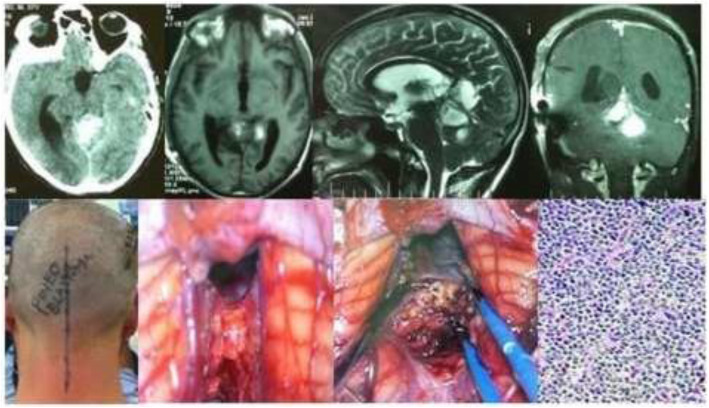

Fig. 6.

A case of a 16-year-old female pineoblastoma showing CT scan, MR images, and intra-operative photos in sitting position. Photomicrograph reveals pineoblastoma cells on a fibrillar network (H&E Stain; × 300)